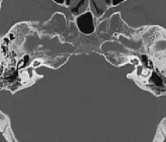

4.4 Comparison with other networks

In this section, the proposed method is compared with 3D-Unet and 3D-DSD. The results of these two methods are shown in Table 2. The results show that the proposed method has higher segmentation accuracy than the other two methods. This improvement is attributed to our proposed 3D dilated convolutional module and the multi pooling module. The visualization results of our proposed method and other methods are shown in Figure 9. The subjective results of our proposed method, the 3D-Unet, and the 3D-DSD. The red labels denote the ground-truth, blue labels, purple labels and yellow labels denote the segmented results of 3D-Unet, 3D-DSD and 3D-MFF respectively. We can see that the result of our 3D-MFF achieved the best.

Refer to caption

(a) 3D-Unet

(b) 3D-DSD

(c) 3D-MFF

Figure 9: The subjective results of our proposed method, the 3D-Unet, and the 3D-DSD. The red labels denote the ground-truth, blue labels, purple labels and yellow labels denote the segmented results of 3D-Unet, 3D-DSD and 3D-MFF respectively. We can see that the result of our 3D-MFF is the best.